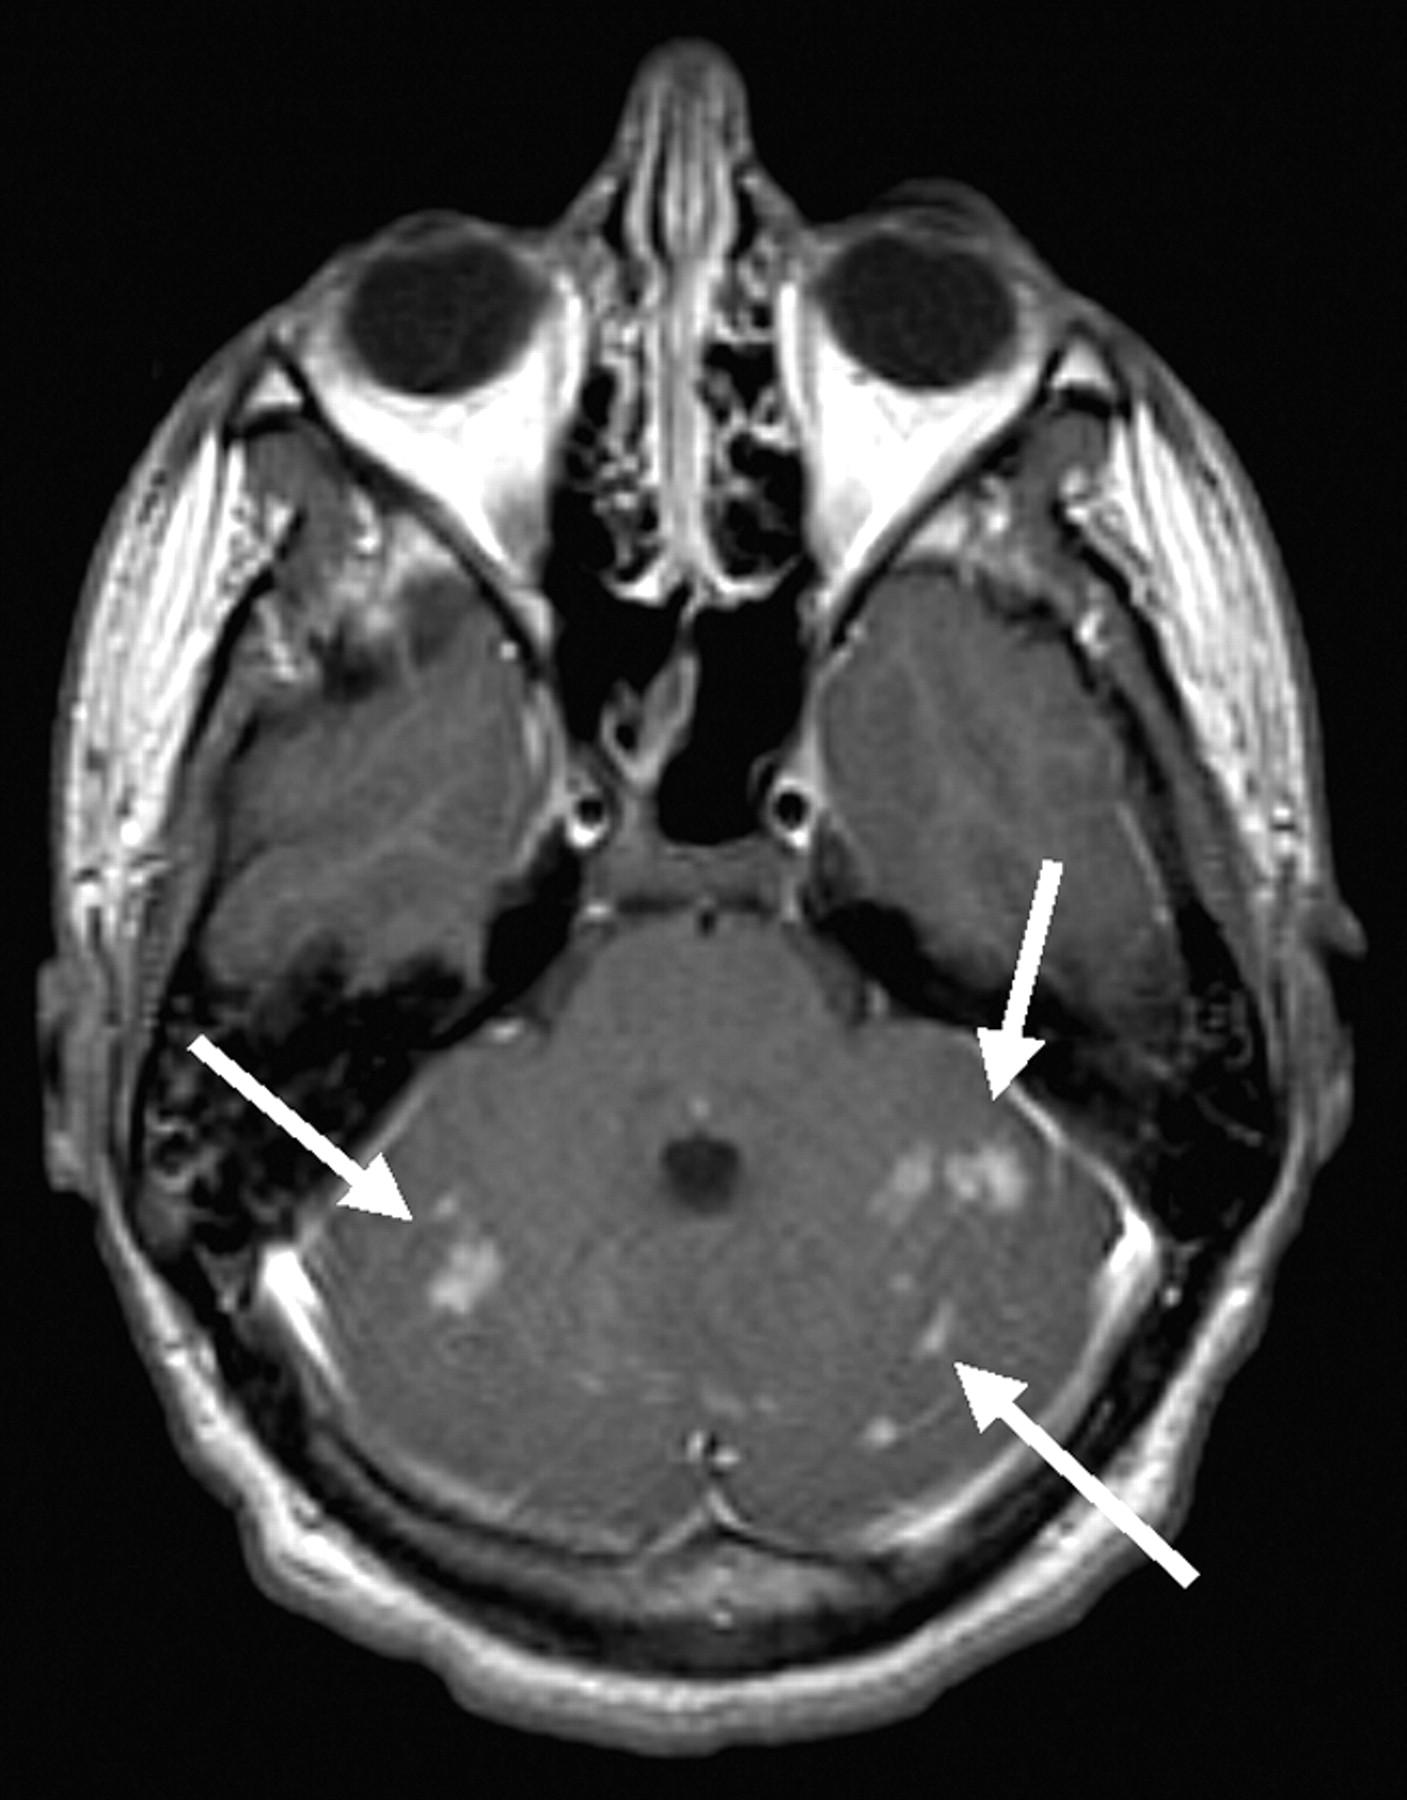

MR imaging of the brain was therefore performed. Proton density–and T2-weighted images revealed hyperintensity of the external capsules and adjacent lateral putamen, the paraventricular nucleus of the thalamus, and scattered areas throughout the cerebellar hemispheres (Fig 1). Pre- and postcontrast T1-weighted images demonstrated T1 shortening and accompanying enhancement only in the supratentorial lesions (Fig 2). T1 shortening in the paraventricular nucleus of the thalamus bordering the third ventricle also extended into the third ventricle, suggesting an underlying hemorrhagic cause, resulting from extracellular methemaglobin (Fig 2). Areas of T2-weighted changes in the cerebellum had corresponding darkness on T1-weighted images but were also noted to enhance after contrast medium administration (Fig 3). These findings suggest an ischemic and hemorrhagic small vessel process, both supra- and infratentorial.

Three axial precontrast contiguous T1-weighted images (A) and corresponding postcontrast images (B) demonstrate both T1 shortening and accompanying enhancement in the same area (arrows).

The MR imaging findings in the present case demonstrate a unique symmetric enhancement, T1 shortening, and T2 prolongation in the external capsules bordering the lateral putamen as well as the thalamus immediately bordering the third ventricle. These cerebral lesions could represent a deep brain manifestation of failure of autoregulation similar to the lesions seen in the 10-month-old patient reported by Akaboshi and Miyashita (11). A pattern of T2 prolongation specifically seen in the external capsules has been reported to be characteristic of, although not specific for, cerebral autosomal dominant arteriopathy with subcortical infarcts and leukoencephalopathy (CADASIL) as well as more sporadically in patients with hypertension. This pattern is consistent with a small vessel process caused by ischemia, demyelination, and axonal degeneration resulting in abnormal T2-weighted signal intensity (12). Specifically in CADASIL patients, these white matter areas of high signal intensity can progress to subcortical lacunar lesions at the gray matter–white matter junction. Subcortical lacunar lesions have the signal intensity of CSF because of leakage of CSF into the widened perivascular space of the small vessels this disease affects (13). To our knowledge, however, the present case reveals T1 shortening as well as T2 prolongation, a unique and distinct supratentorial manifestation likely reflecting the ischemic and hemorrhagic intracranial effect of heat stroke.

The differential diagnosis for bilateral high signal intensity in the external capsule and lateral putamen on T2-weighted images includes not only CADASIL and hypertension, but also methanol toxicity and, rarely, Wilson disease (15, 16). The symmetric T1 shortening in this location, however, is unique to this case and again likely reflects a very specific hemorrhagic consequence of an underlying ischemic process uniquely affecting these areas as well as those in the thalamus immediately adjacent to the third ventricle. Such T1 shortening has been described in neurofibromatosis and liver failure but typically involves more medial structures such as the globus pallidus and thalamus (17, 18). Although the T1 shortening could alternatively relate to the patient’s transient liver dysfunction, the pattern of spread into the third ventricle and exclusively extreme lateral and medial deep gray matter involvement are not typical of this or any of these previously described metabolic (nonhemorrhagic) scenarios of T1 shortening.

The symmetric medial thalamic lesions correspond to the paraventricular nucleus. This is known to be intimately associated with the systems that regulate core temperature, metabolism, and energy balance via the hypothalamic-pituitary-adrenal axis (19). It is therefore likely that abnormal signal intensity in this structure relates to the excess demands placed upon it in the setting of this patient’s acute hyperthermia. Such increased local metabolic demands could therefore have outstripped the capabilities of the blood supply to this region, compounded by impaired cerebral perfusion, resulting in ischemic, hemorrhagic effect.